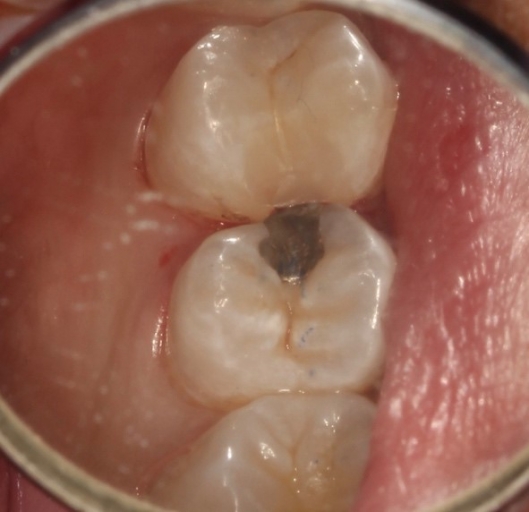

Subgingival margins are a common clinical challenge. In these cases, deep margin elevation can be a useful technique to help restore teeth to their proper form and function.

What is deep margin elevation? In essence, this procedure involves placing a material to raise the restorative margin to an equigingival or supragingival location. Some of the earliest work published on the concept came from Dietschi and Speafico in 1998.

Since Magne reintroduced the concept, deep margin elevation has been gaining popularity as a way to raise indirect restoration margins supragingivally, especially for intraoral scanning. Margin elevation can be performed using a host of different materials, such as composites, glass ionomers or resin-modified glass ionomers.

Typically, a post-op bitewing is taken to confirm the proper adaptation of restorative material to tooth structure, mainly when deep margin elevation is used to elevate a margin for indirect restorations. Deep margin elevation can be utilized near the bone with negligible effects on the biologic width when performed in a limited area.